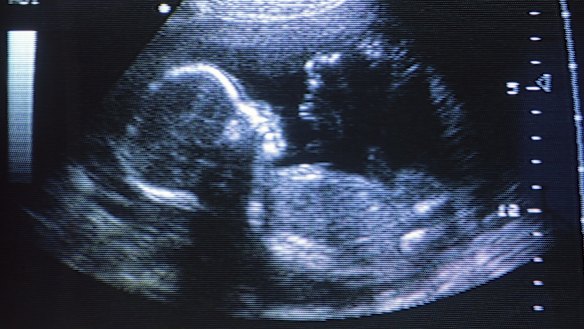

You can do this two ways. The first is to completely replace the baby's blood at birth. The second is to begin treatment even earlier – which is how Mannix-Power came to have fortnightly intra-uterine transfusions from her 20th week of this fourth pregnancy, in which Challis and his team, guided by ultrasound, used a long needle to trickle new blood into the umbilical vein in her daughter's liver.